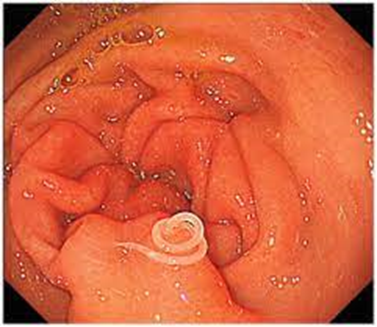

8. Sashimi / Anisakiasis